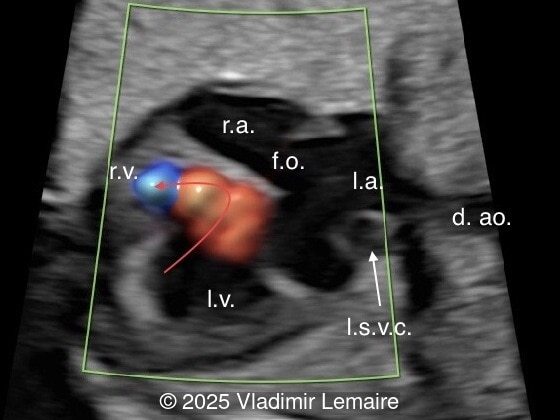

We present a case of isolated tricuspid atresia type 1 with persistent left superior vena cava. No other extracardiac anomalies were found. Our diagnosis was confirmed after birth.

In the images below, the abbreviations are as follows: RA: right atrium; RV: right ventricle; LV: left ventricle; MV: mitral valve; LA: left atrium; FO: foramen ovale; SVC: superior vena cava; LSVC: left superior vena cava; PV: pulmonary veins; PA: pulmonary artery; MPA: main pulmonary artery; RPA: right pulmonary artery; AO: aorta; dAO: descending aorta; aAO: ascending aorta; DA: ductus arteriosus; T: trachea; * marks the ventricular septal defect.

The four-chamber view in tricuspid atresia is diagnostic. It reveals a small right ventricle, a ventricular septal defect, and the absence of a right-sided atrioventricular junction. The size of the right ventricle mainly depends on the size of the ventricular septal defect: the smaller the ventricular septal defect, the smaller the right ventricle. Its contractility is normal with no myocardial thickening. The atretic tricuspid valve appears as echogenic thickened tissue and the right atrium is slightly dilated. The interatrial communication is large and there is often a redundant flap of the septum secundum that bulges into the left atrium. The interatrial and interventricular septa are malaligned.

Color Doppler confirms the diagnosis on grayscale ultrasound, as it demonstrates the lack of blood flow across the tricuspid valve and a patent mitral valve. Due to increased blood flow across the mitral valve, aliasing is typically noted on color Doppler. Mitral valve regurgitation has been associated with a poor outcome. The right ventricular cavity is filled in late diastole from the left ventricle, through the ventricular septal defect. Left-to-right shunting across the ventricular septal defect can be seen on color Doppler. Color Doppler is helpful in the evaluation of flow across the great arteries. Flow across the pulmonary artery is generally antegrade. Pulmonary stenosis should be suspected when the vessel is diminutive in size rather than the demonstration of turbulent flow on color Doppler, which is typically absent in these cases.